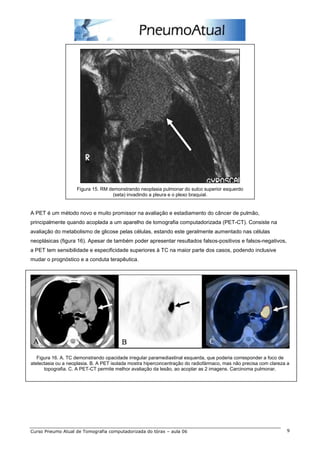

Figura 15. RM demonstrando neoplasia pulmonar do sulco superior esquerdo

(seta) invadindo a pleura e o plexo braquial.

A PET é um método novo e muito promissor na avaliação e estadiamento do câncer de pulmão,

principalmente quando acoplada a um aparelho de tomografia computadorizada (PET-CT). Consiste na

avaliação do metabolismo de glicose pelas células, estando este geralmente aumentado nas células

neoplásicas (figura 16). Apesar de também poder apresentar resultados falsos-positivos e falsos-negativos,

a PET tem sensibilidade e especificidade superiores à TC na maior parte dos casos, podendo inclusive

mudar o prognóstico e a conduta terapêutica.

Figura 16. A. TC demonstrando opacidade irregular paramediastinal esquerda, que poderia corresponder a foco de

atelectasia ou a neoplasia. B. A PET isolada mostra hiperconcentração do radiofármaco, mas não precisa com clareza a

topografia. C. A PET-CT permite melhor avaliação da lesão, ao acoplar as 2 imagens. Carcinoma pulmonar.